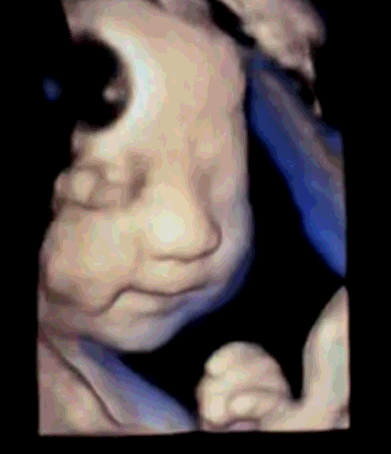

与胎宝紧密相连280天里,一次次胎动是你们之间独特的交流方式,而这时,我们更加好奇胎宝每天都在妈妈肚子里干什么呢?看看这些四维彩超抓拍的胎宝的小模样吧!以下为胎宝的自白时间哦~!

“Hi,妈妈,第一次看到我是不是很惊喜,很幸福~

在刚刚医生阿姨为我做检查时,我能感受到您一直紧绷着,所以,当听见您要见到我第一面的时候,我要送给您一个我的招牌动作~还告诉您一个秘密哦~知道您们在看我,我也很开森~”

但通过美琳达的四维彩超画面中

TA们的活泼好动,萌萌的表情

已经说明了一切